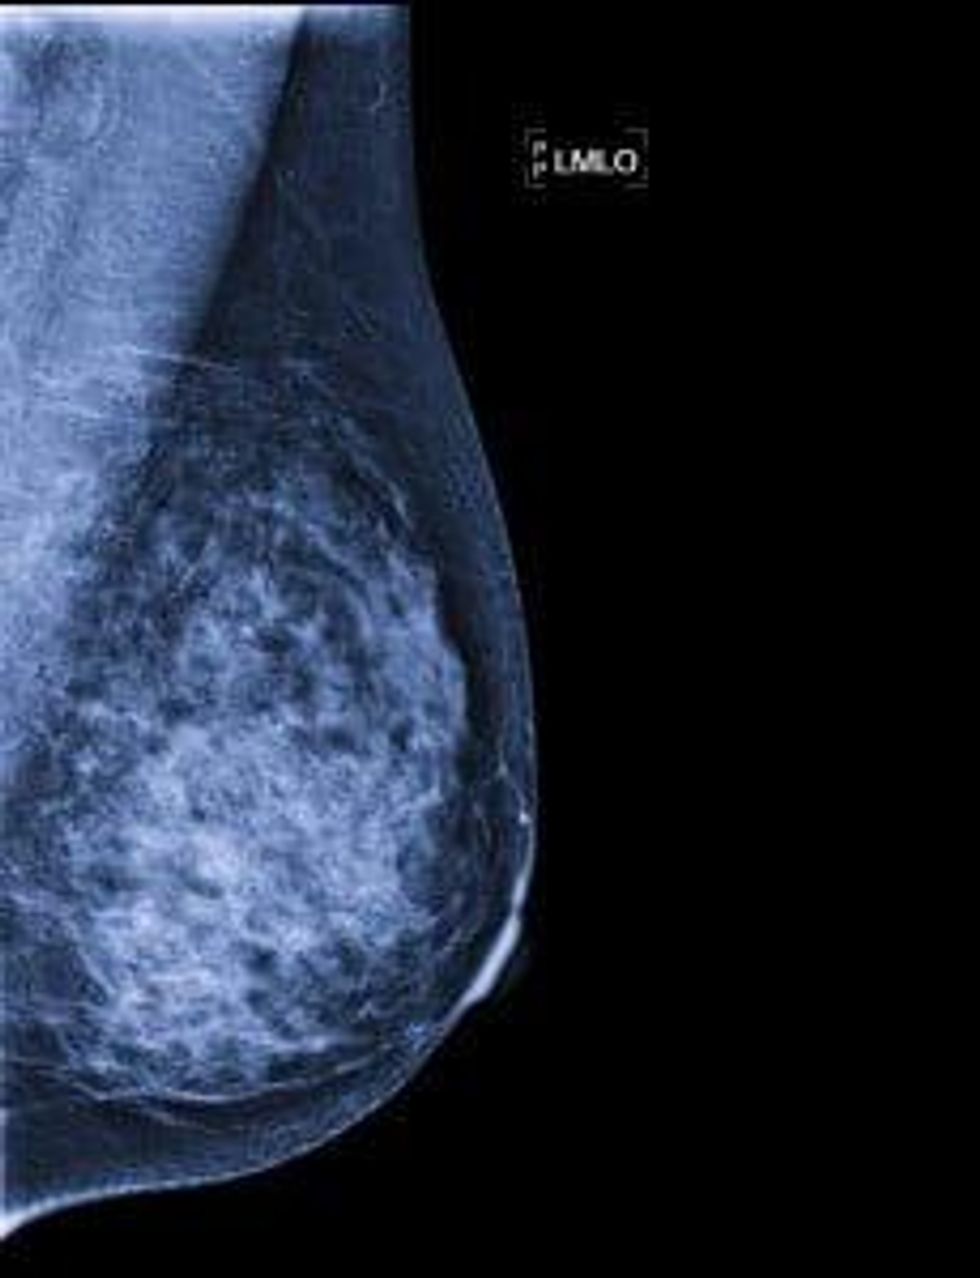

How about in this photo?

3. There are new and innovative ways to diagnose breast cancer. Here's a look at some options: